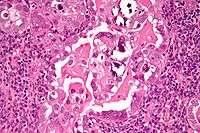

Micrograph of uterine serous carcinoma demonstrating characteristic psammoma bodies and cilia. H&E stain.

Histopathologically, uterine serous carcinomas is typically characterized by (1) nipple-shaped structures (papillae) with fibrovascular cores (2) marked nuclear atypia (irregularies in the nuclear membrane, enlarged nuclear size), (3) psammoma bodies and (4) cilia.